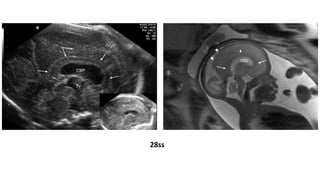

TRANSTORNOS DE PROLIFERACIÓN: MACROCEFALIA

28ss

Editor's Notes

• #22 Figure 2 Patient 15. (a) Midsagittal transvaginal ultrasound image at 28 weeks showing thick and echogenic corpus callosum (arrows), and large cavum septi pellucidi (CSP) and third ventricle (3V). Inset (b) Normal corpus callosum at the same gestational age. (c) Midsagittal magnetic resonance image taken 2 days later showing the abnormal callosal genu and splenium (arrows). Note that the body of the corpus callosum is not well depicted in this image (small arrow). The serrated pattern of the parietal cortex (arrowheads) is indicative of the presence of polymicrogyria.

• #26 Figure 3 Patient 5, hemimegalencephaly. (a) Axial transabdominal ultrasound image at 28 weeks showing asymmetrical brain hemispheres with unilateral ventriculomegaly, and abnormal cortex and Sylvian fissure (arrow). (b) Sagittal plane obtained during the same examination showing frontal bossing and thick corpus callosum (arrows). (c) Fetal and (d) neonatal magnetic resonance images showing the abnormal cortex of both hemispheres and thick frontal cortex with polymicrogyria (arrows).